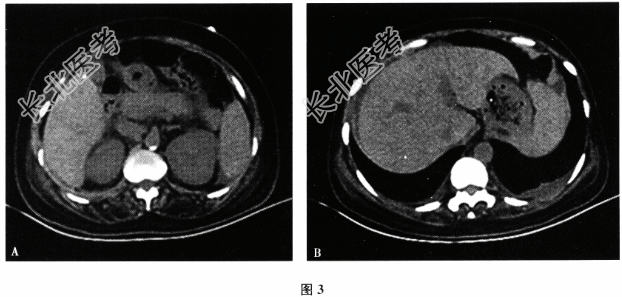

- 多项选择题5.【提示】患者入院后出现上腹痛加重,无尿, 24小时尿量20ml,查体; 心率40次/分,双肺呼吸音粗, 腹软,上腹中部压痛, 无肌紧张及反跳痛。实验室检查:血尿素氮30. 31mmol/L, 肌酐519.2μmol/L,血钾3.97mmol/L, 血钠127.8mmol/L,淀粉酶728.2U/L, 脂肪酶947. 7U/L。腹部CT(图3A):示双肾轮廓增大, 肾周渗出积液;胰腺轮廓模糊, 周围渗出,注意胰腺炎。腹部盆腔多发渗出积液, 脾大。双侧胸腔少量积液(图3B)。